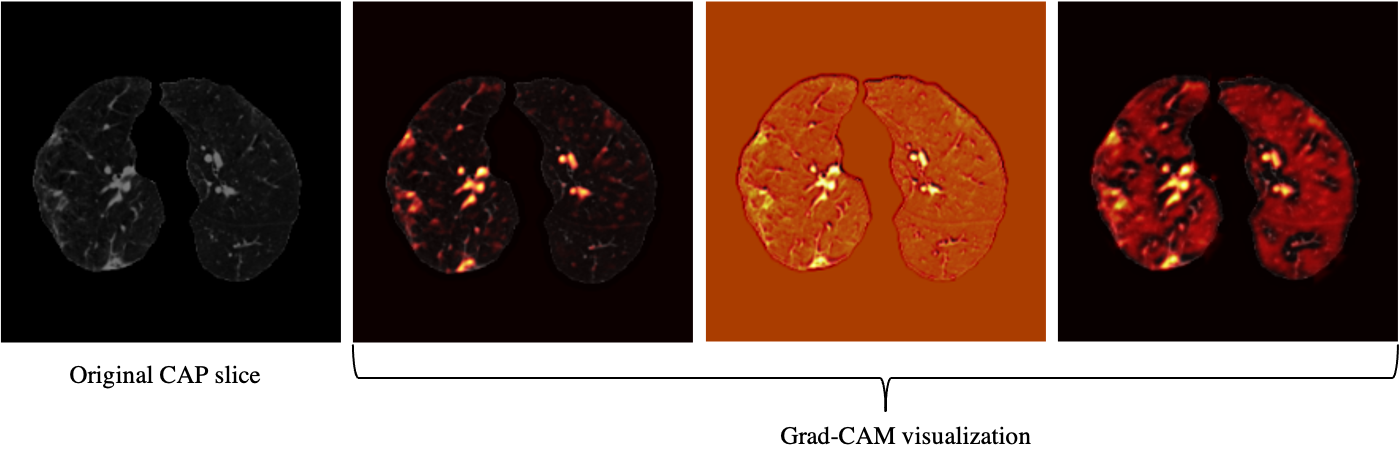

Figure 4: Grad-CAM visualization of one CAP slice. This figure shows that the proposed AI model is paying attention to relevant locations of the image.

Based on the CT scans only, we analyzed the misclassified COVID-19 cases through all folds (11 cases in total), and studied their relation with the disease severity, coming to the conclusion that 4 out of 11 cases, did not have any related imaging findings, 5 were scored 1 by the three radiologists, one was scored 2, and only one case was scored at 3, which means the developed model is less likely to misclassify severe cases. Neither the developed model nor the experienced radiologist was able to detect the 4 COVID-19 cases without imaging findings, using CT scans only. Furthermore, since the CAP patients come from a different cohort and scanned with a standard dose, we visualized the model’s output for CAP cases, one of which is shown in Fig. 4, using Grad-CAM localization technique. This figure shows that the model is paying more attention to disease-related regions of the image, rather than dose-related ones. We performed the same localization technique on two slices with infection of the same COVID-19 patient, shown in Fig. 5.